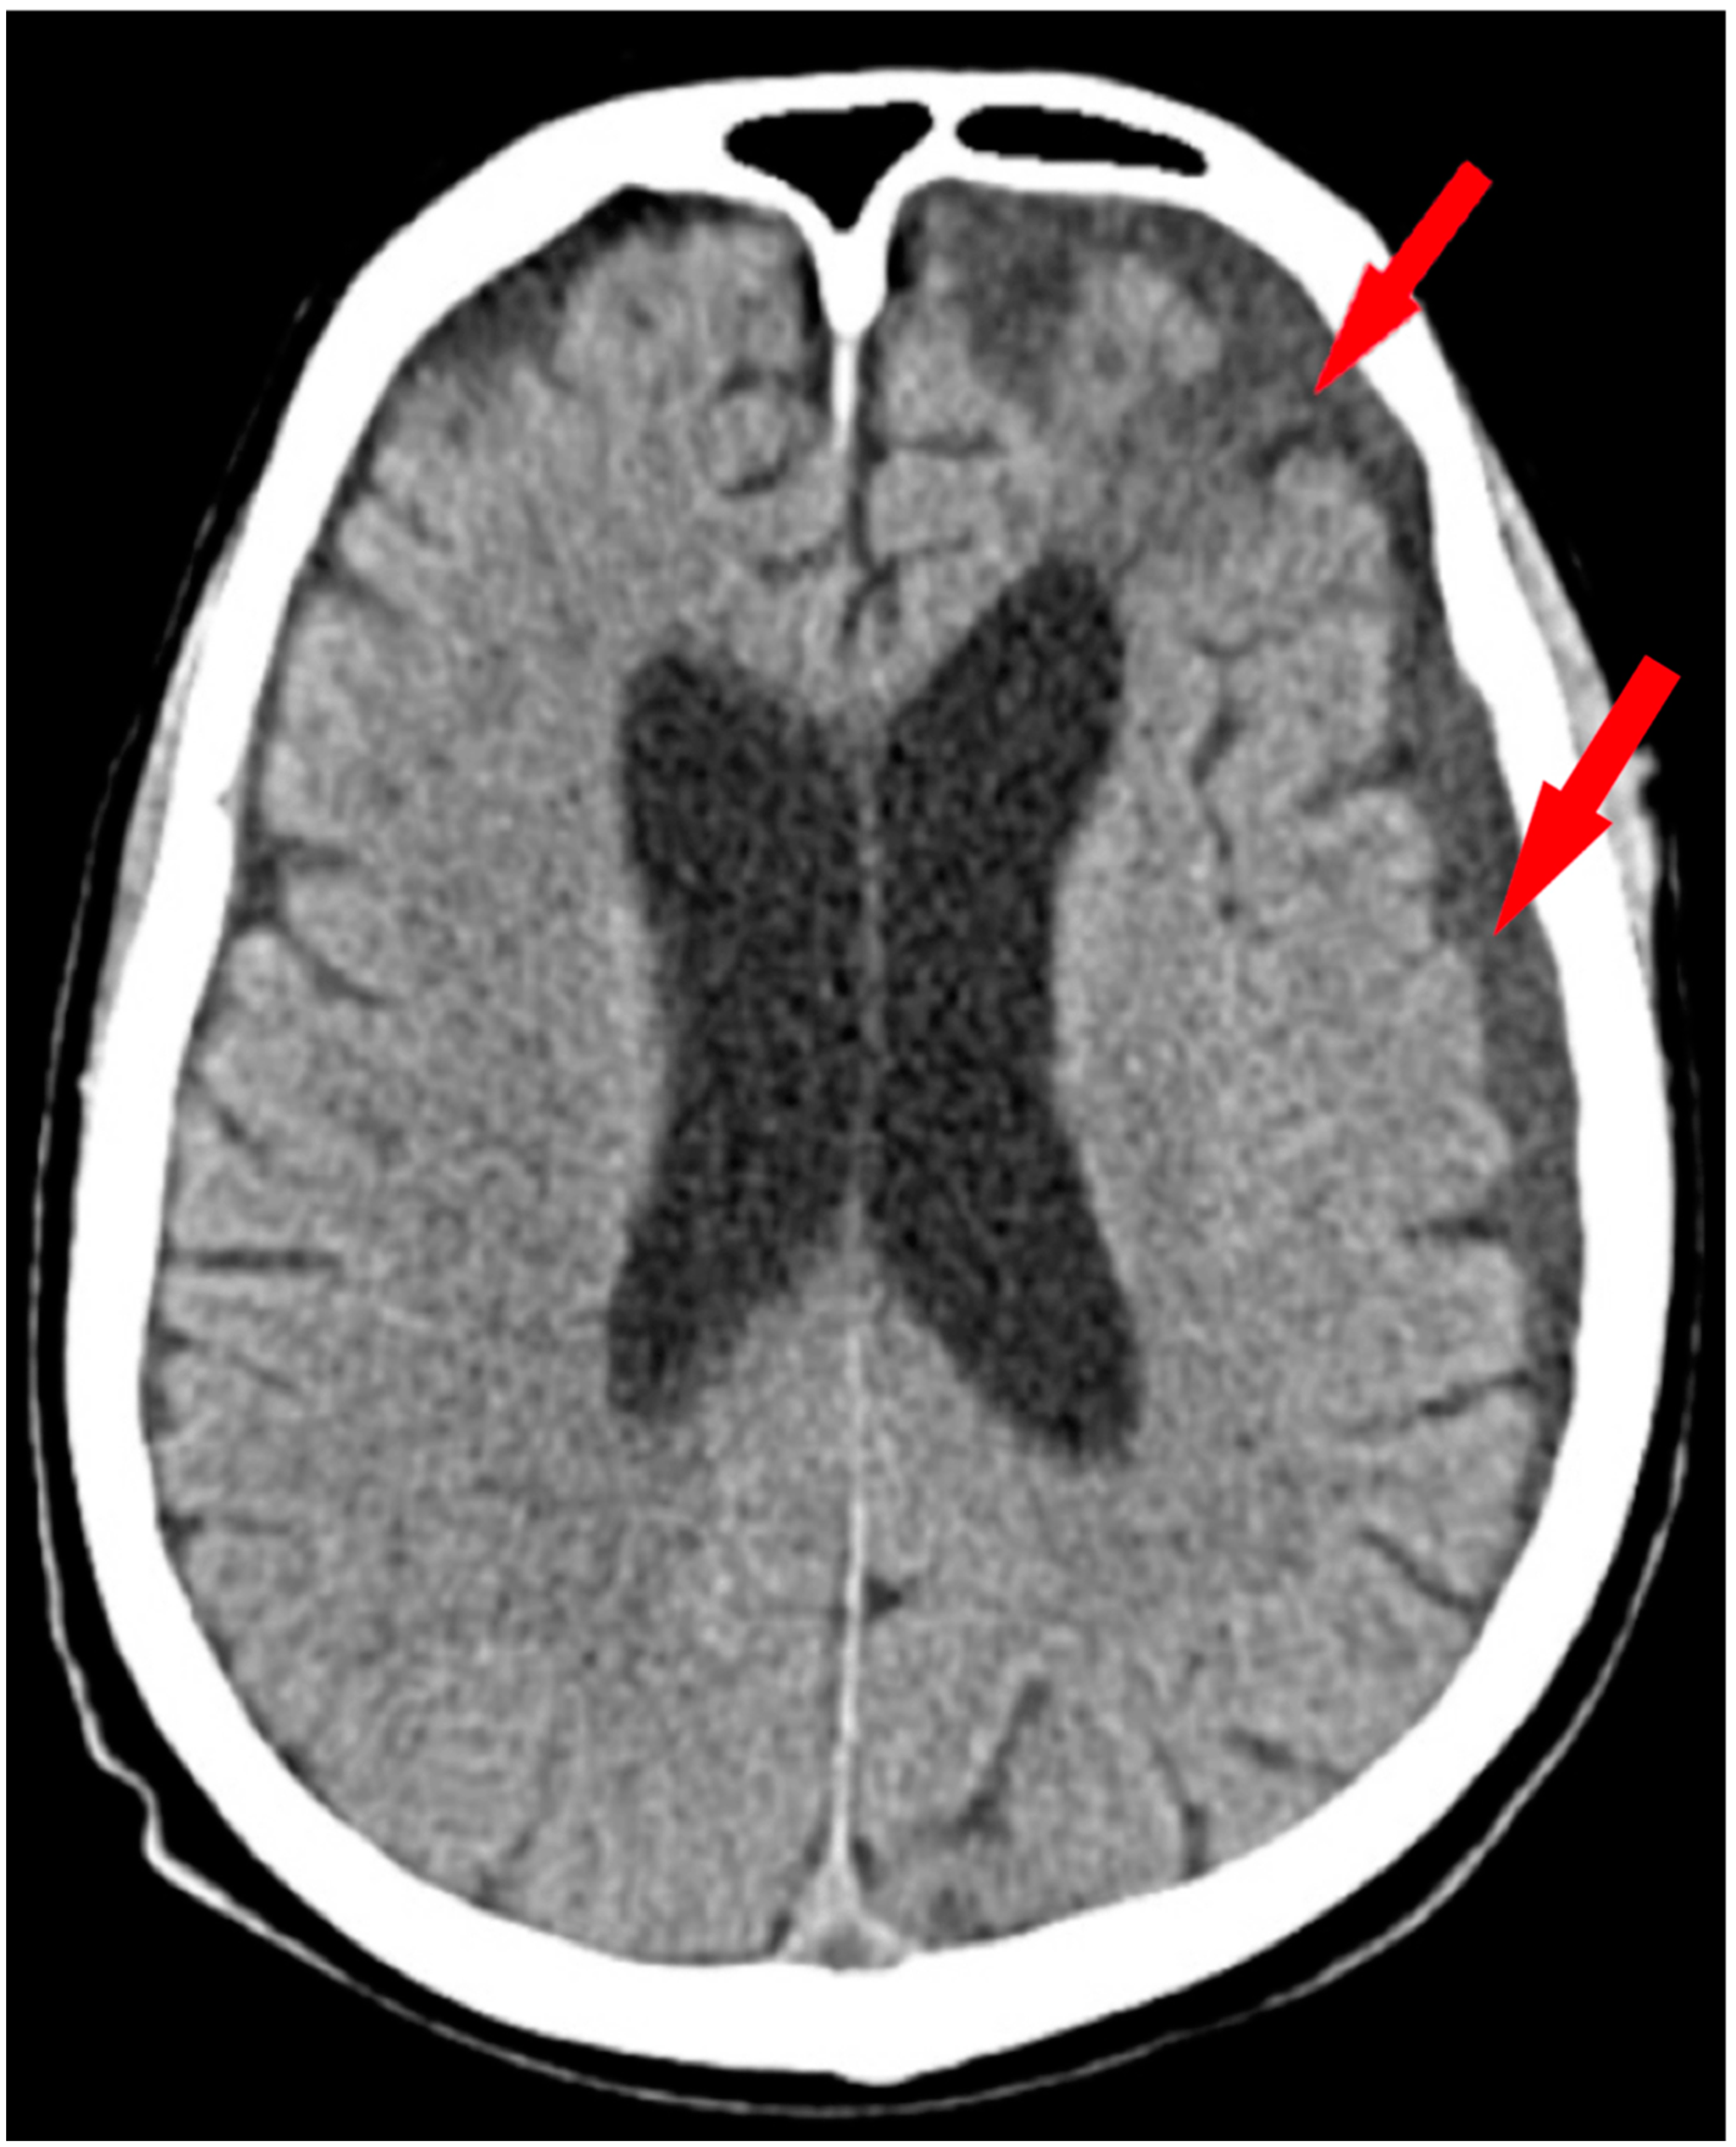

2. Case Presentation